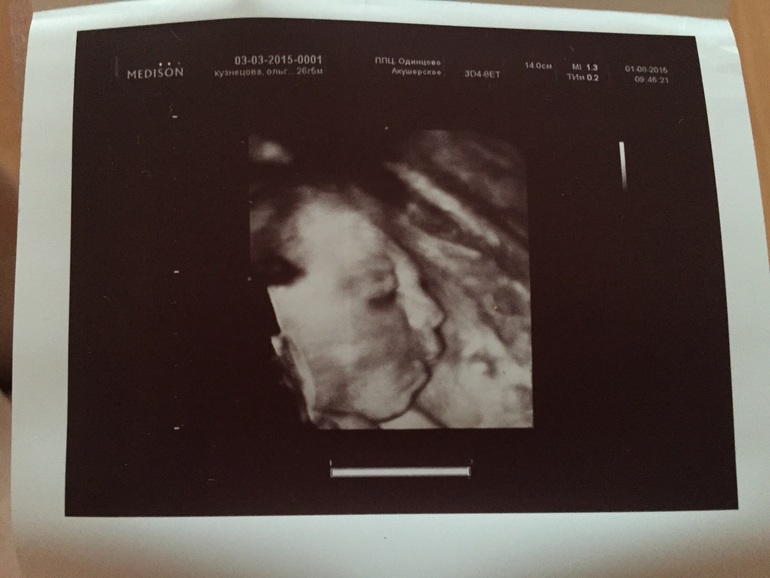

Вопросы про УЗИ, обследования и анализы: что, где, как, когда?Не приплюснутое ли лицо у малыша?

Мне кажется немного странным нос....

28 недель

Просто на УЗИ в 12 недель врач намерила длину носовой кости 17, говорит "мало", перемерила, говорит "вооооот, теперь 19, нормально".... И после этих её предложений я не нахожу себе покоя до сих пор....

В УЗИ 28 недель написано про лицо - постановка глазниц правильная, хрусталики определяются, носогубный треугольник, верхняя и нижняя челюсти сформированы правильно.